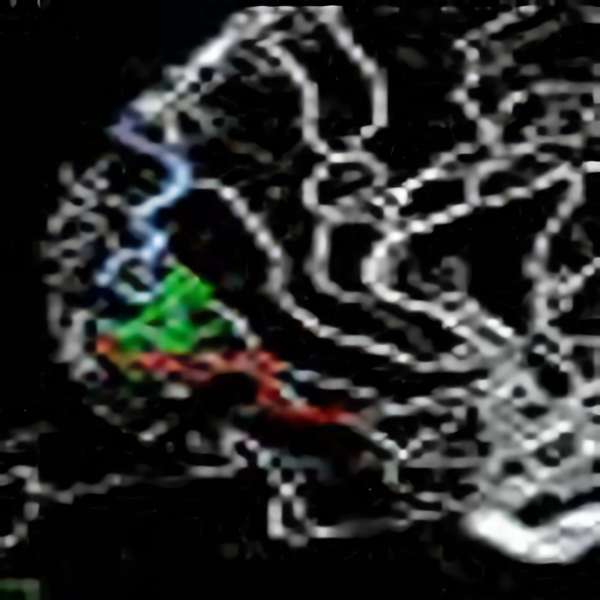

手術中

モニタリング

脳血管撮影

手術前

手術後